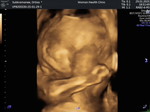

15 พ.ค ค่ะ ยังเงียบยุเลย แล้วก็แอบกังวลกลัวคลอดเองไม่ได้ไปซาวด์มาล่าสุด37 วีค หนัก3000อิแม่จิเป็นลมกลัวคลอดไม่ได้555